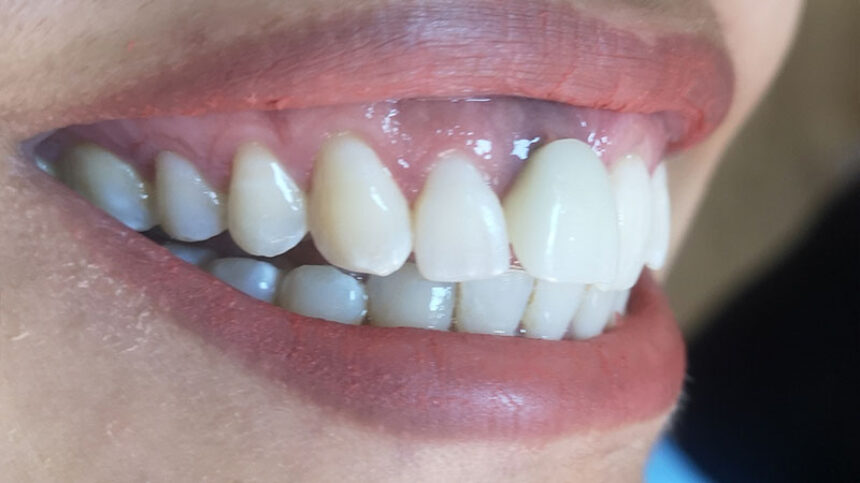

Εισαγωγή Ανάμεσα στα πιο συνήθη προβλήματα στην σύγχρονη οδοντιατρική είναι αυτό της αποκατάστασης της οδοντικής [...]